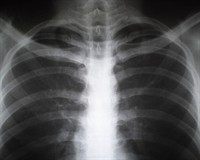

Флюрографія — це рентгенографія легень, яку роблять з метою дослідити стан легень.

Під час флюрографії кістки також відображаються на знімку білим кольором, а повітря чорним. Також на знімку буде видно серце, через його структурні особливості.

Щоб знімок вийшов чітким людині потрібно не дихати під час тих кількох секунд, коли робиться знімок, для цього потрібно зробити глибокий вдих, щоб легені розкрилися та затримати дихання.